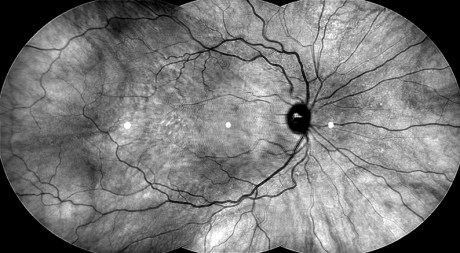

Entoptic phenomena are forms that originate within the human visual system. There has been research into the similarity of these geometric patterns that appear on our inner eyes when they are closed and the sort of shapes and marks made in paintings by societies that practise altered states of consciousness through religious, shamanistic or drug induced means often in the dark depths of caves. Our physiognomy hasn’t changed in 40,000 years so we can still experience floating shapes within our eyes, how we respond to these optical hieroglyphs depends on our culture and transcendental interpretations.